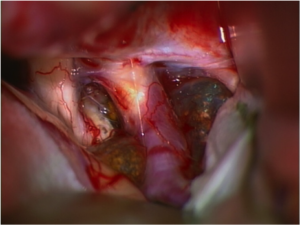

Intraoperative Bilder einer Operation eines Kraniopharyngeom vor und nach Tumorentfernung mit freier Sehnervenkreuzung (Chiasma).

Intraoperativer Aspekt eines Optikusscheidenmeningeoms (Typ 2a) mit Durchwachsen des Meningeoms durch den Sehnervenkanal in den intrakraniellen Raum; Operation über einen Transkranieller operativer Zugang bei einem bis in den Gehirnraum wachsenden Opticusscheidenmeningeom [TU] (linke Seite), nach Tumorentfernung mit entlastetem Sehnerven [SN] und befreitem Hirngefäß [ACI] (rechte Seite).